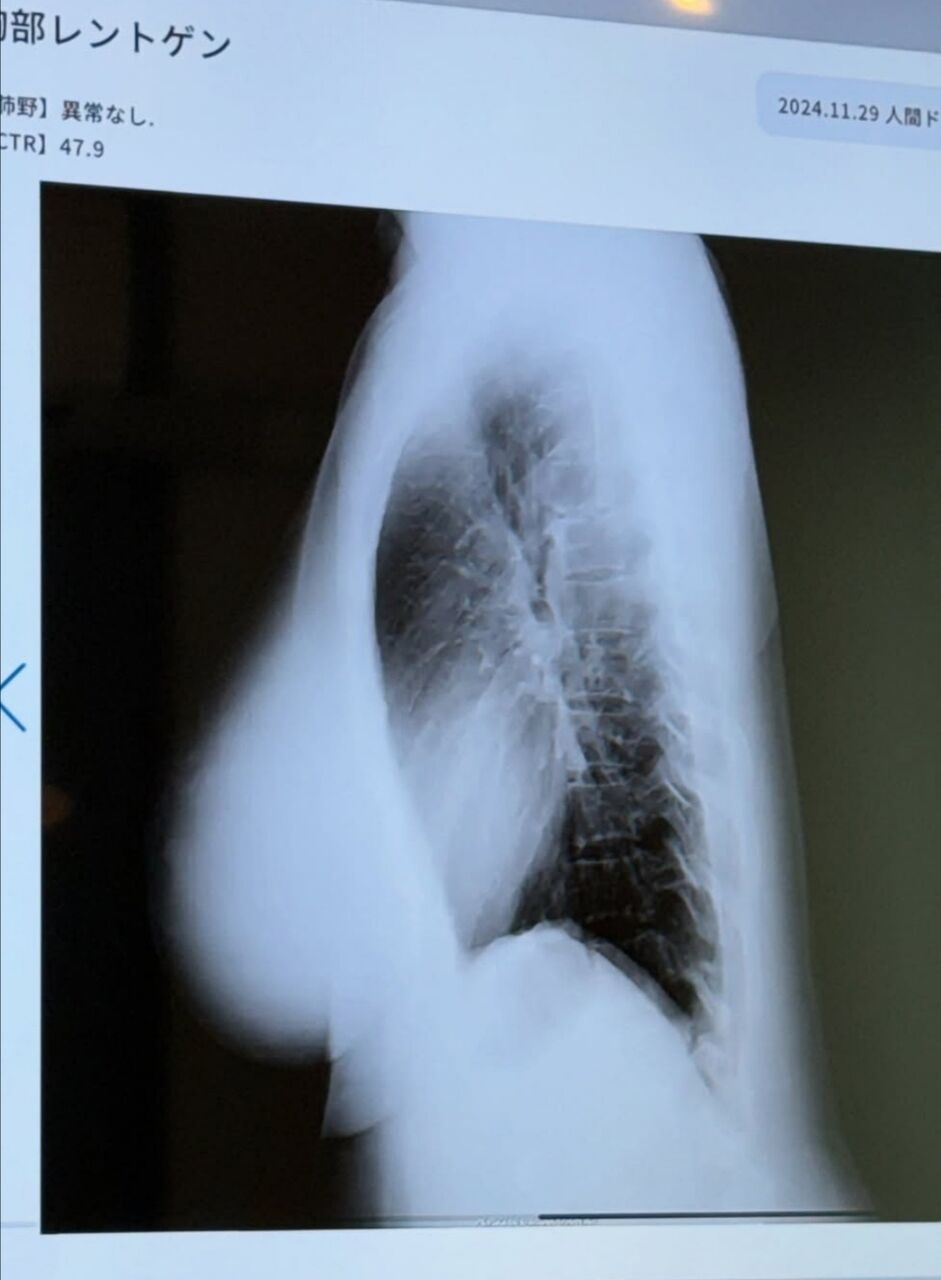

天木は「25歳ぶりに人間ドック 今年は肺のCTを撮った時の写真をお見せします!肺の上にぷるるんと天乳が見えますね」と胸部のエックス線写真を公開し「お腹減ってお胸は減らない 完璧です」とつづった。